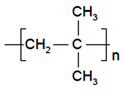

| Polymers | Structure | Fabrication Method | Commercial Products/Literatures | Comments | Reference |

|---|---|---|---|---|---|

| Polycarbonate (PC) |  | Ion-track etching | Estrogen | Excellent stability against oxidation and biodegradation and improves antifouling properties | [151] |

| Polyethylene (PE) |  | Ion-track etching | Catapress (Clonidine), Boehringer IngelheimClimara (Estradiol), Berlex | Physico-chemical stability andordered pore formation with superior membrane performance | [152] |

| Polyethylene terephthalate (PET) |  | Lithography | Ketoprofen | Biostable, antifouling, has better performance of membranes, in useful in preparing surgical meshes and ligaments | [153] |

| Polystyrene (PS) |  | Lithography | d-limonene, ibuprofen | Chemical resistance, easy processing, lower cost, exhibits enhancements in strength, stiffness, toughness, and ductility | [154] |

| PC, PE | - | Ion-track etching | Estraderm (Nitroglycerin), Rotta Research | Cost-effective and biocompatibility is fairly good | [155] |

| PC, PE, PET, PS | - | Phase separation | Deponit (Nitroglycerin), Pharma SchwarzHabitrol (Nicotine), Novartis | Cost-effective and biocompatibility is fairly good | [154,156] |

| Polyurethane (PU) |  | Sol-gel/solvent casting | Vivelle (Estradiol), Novartis | Good elasticity, biodegradable, suitable for hydrophilic drugs, biocompatibility is fairly good | [154] |

| Polysiloxane (silicone) |  | Sol-gel/solvent casting | Prostep (Nicotine), Lederle, Transderm Nitro (Nitroglycerin), AlzaSyncro-Mate-C (Norgestomet) | Better insulation, excellent biocompatibility, and fabricated easily for hydrophilic drugs | [157] |

| Polyisobutylene (PIB) |  | Solvent casting | Aminopyrene, Mitsubishi Petrochem Co., Japan | Good adhesive drug impermeable layer and high degree of tack or self-adhesion | [158] |

| Polymethyl methacrylate (PMMA), poly (2-hydroxy ethyl methacrylate) |  | Layer by layer deposition | Androderm (Testosterone), SmithKline Beecham | Physical strength and transparency | [159] |

| Polyvinyl alcohol (PVA), Poly (ethylene-co-vinyl acetate) |  | Solvent casting | Nitro-Dur I (Nitroglycerin), Key PharmaTestoderm TTS (Testosterone), Alza | Rate-controlling membranes, high membrane permeability, hydrophilicity and strength, suitable for lipophilic drugs | [160] |

| Polyacrylic acid, polyacrylate, polyacrylamide |  | Layer by layer deposition | Epinitril (Nitroglycerin), Rotta ResearchMonsanto (Fentanyl), Dow Corning | Good adhesivity and spreadability and contains a drug impermeable layer | [160] |

| Polylactides (PLA), polylactic-co-glycolic acid (PLGA), polyglycolides (PGA) |  , ,  | Sol-gel/solvent casting | Propranalol, Exxon Chemical Co. | Good biocompatibility; lactic and glycolic acids are the degradation products and they are easily eliminated from the body | [161,162] |

| Polyvinyl pyrrolidone (PVP), poly (N-vinyl pyrrolidone) |  | Sol-gel/solvent casting | Cytarabine, ara-ADA, Polyscience | Superior biocompatibility, has suspension capabilities, antinucleating agent, and enhances release rate | [163] |

| Polyethylene glycol (PEG) | Sol-gel/solvent casting | Miconozale, Rohm, Germany | Chemically inert and free of leachable impurities | [164] | |

| Oxide plus polymer | - | Sol-gel/solvent casting | Superior biocompatibility and has narrow pore size | ||

| Polymer coating on support membrane | - | Layer by layer deposition | [165] |